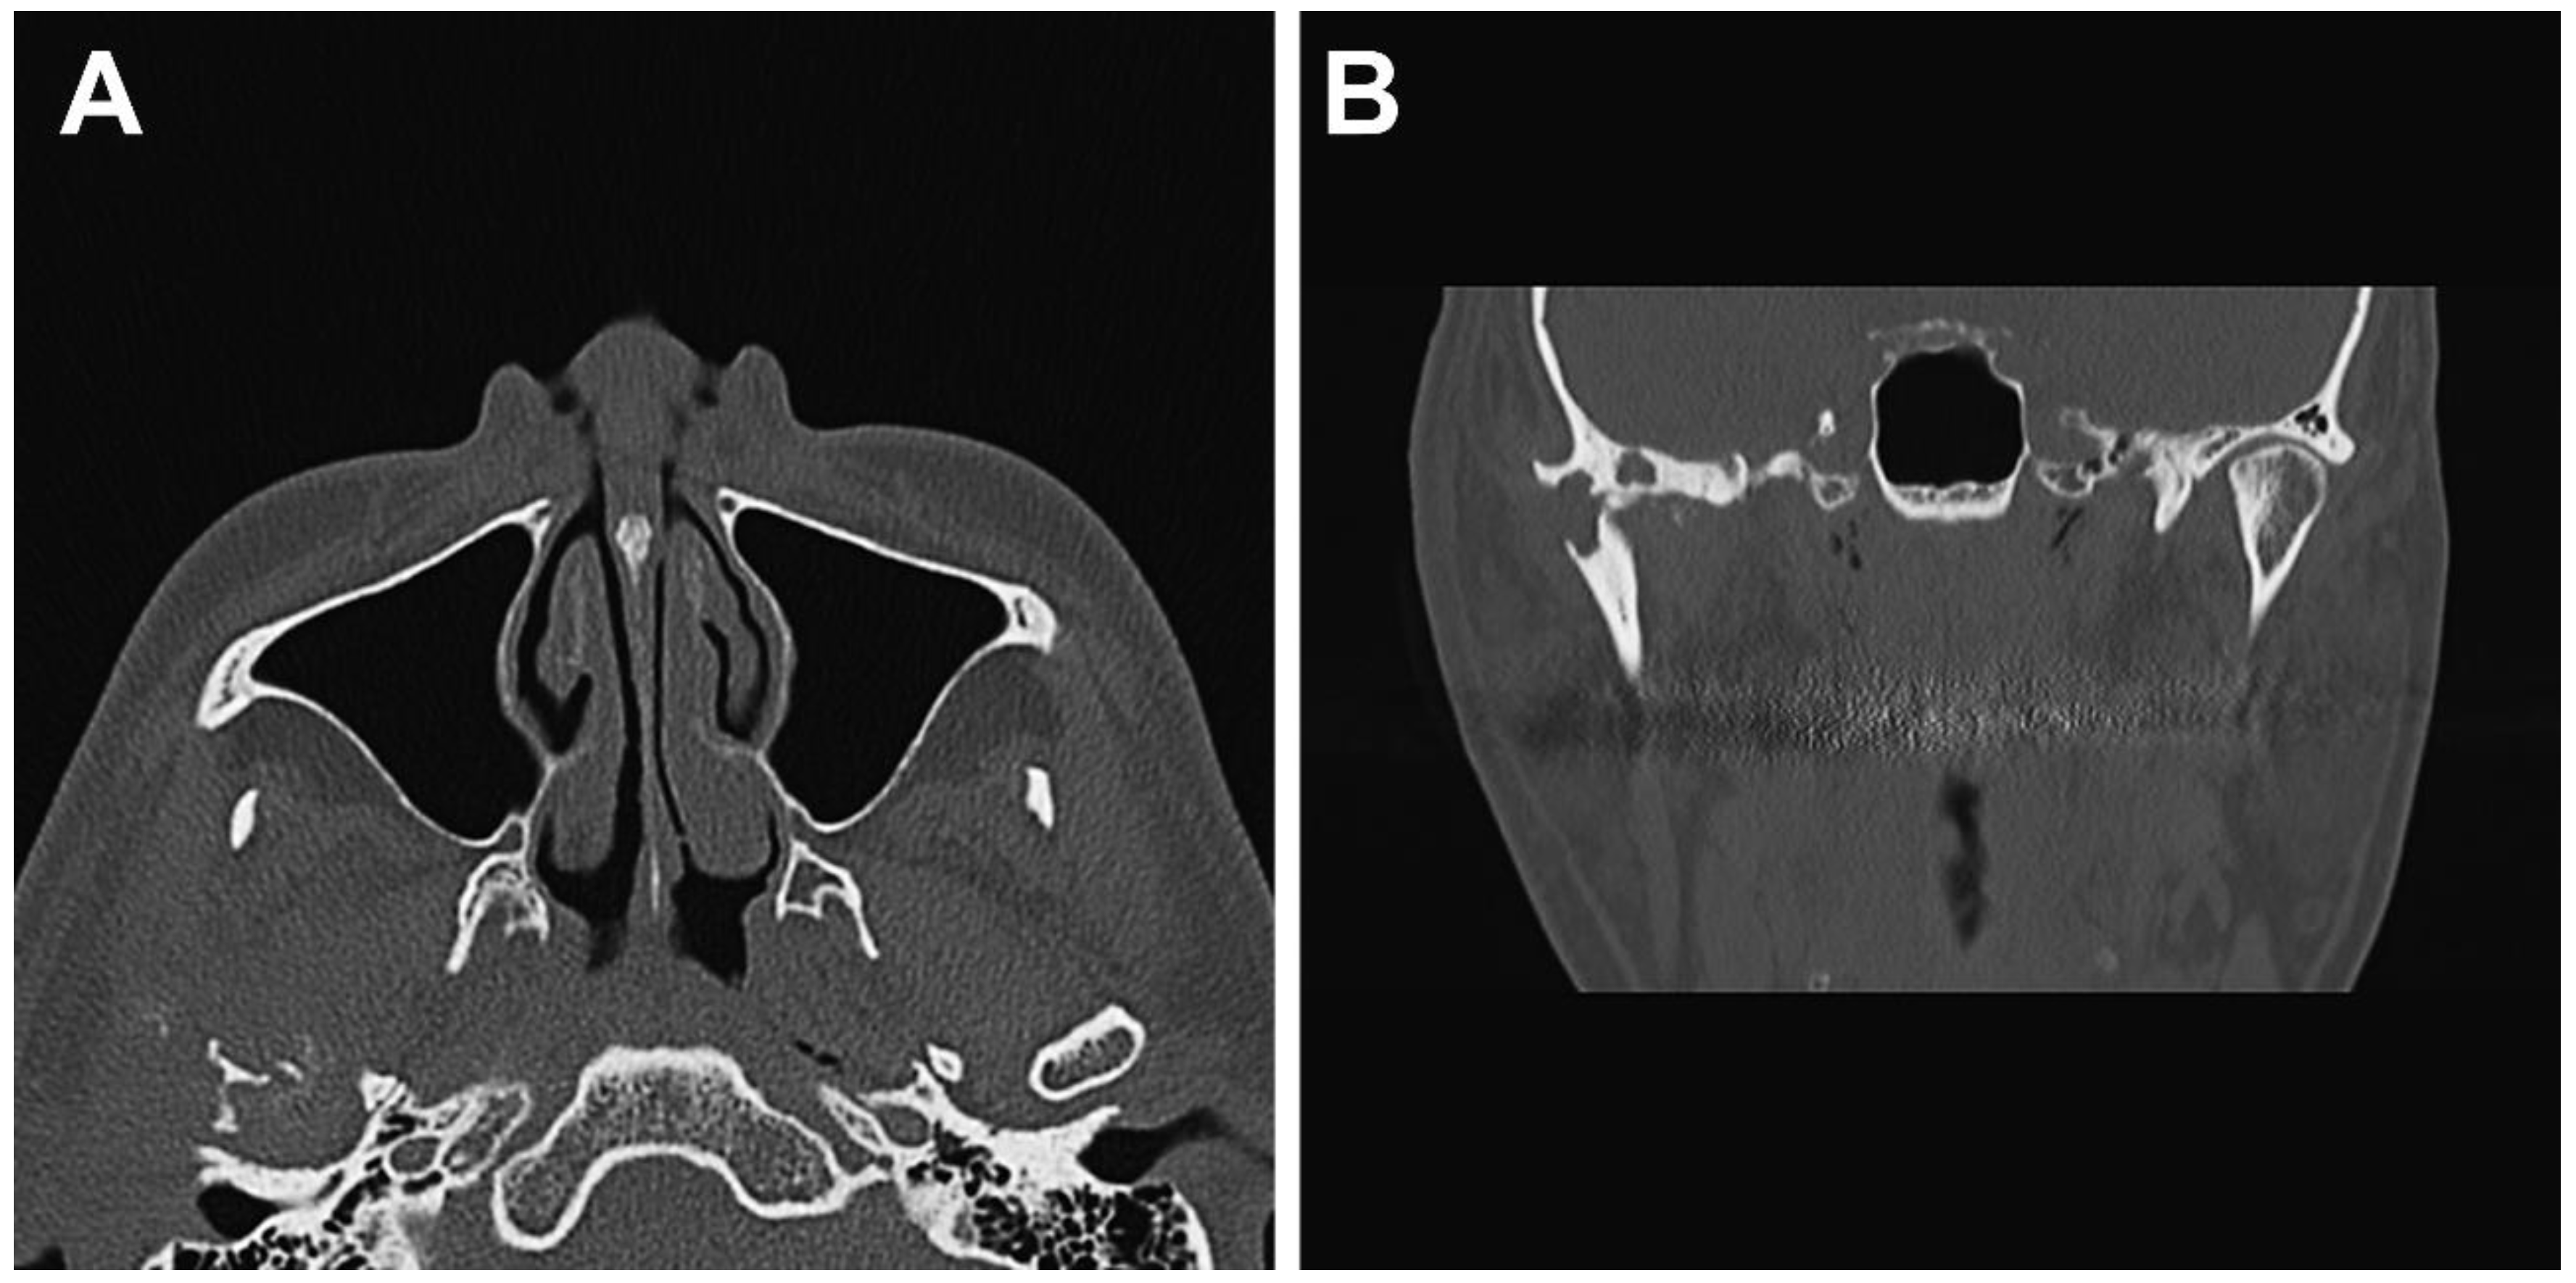

2.1. Clinical Summary

2.2. Pathological Findings